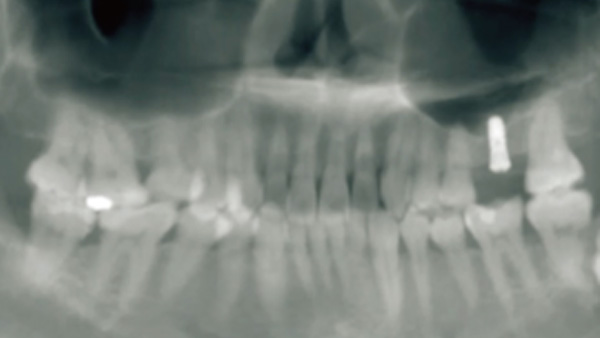

覆蓋所有牙位、即刻種植、即拔即種、全口無牙頜種植